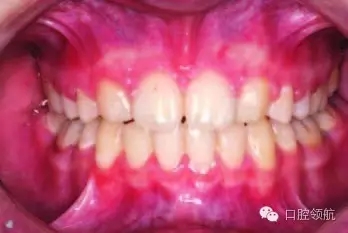

正畸治療結束后,尖牙是如何被改形的呢(圖3.7)?

使用復合樹脂材料在尖牙上堆塑出側切牙的近中尖。